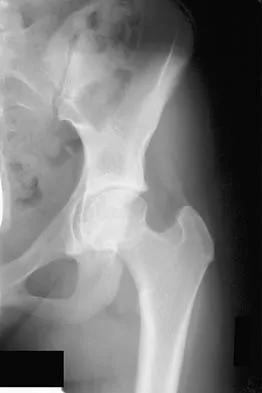

High-yield MCQs for Set 1 on Hip & Knee Reconstruction, perfect for AAOS & ABOS board review. Covers arthropl…